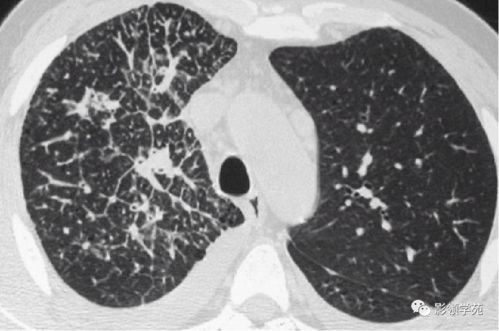

更为严重的是,艾滋病感染者可能会出现各种机会性感染和肿瘤。这些并发症可能涉及多个器官系统,如肺孢子菌肺炎、隐球菌性脑膜炎、结核性脑膜炎等。口腔可能出现一系列问题,如口腔念珠菌感染、口腔溃疡等。恶性淋巴瘤和卡波西肉瘤等肿瘤也可能出现。这些症状的出现都是艾滋病病毒感染的严重表现,需要引起高度警惕。